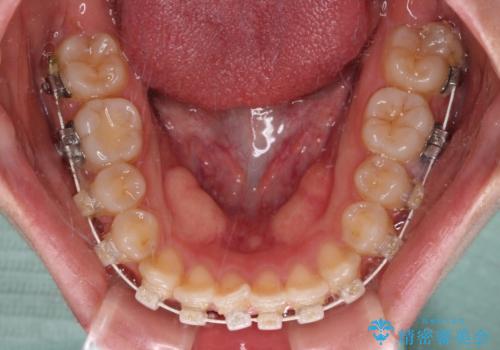

- 矯正装置

- 審美装置

- 1年1ヶ月